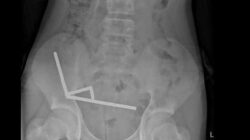

Pada November 2020, Maradona dirawat di rumah sakit setelah mengalami masalah kesehatan. Pemeriksaan di klinik Olivos dan Ipensa Sanatorium di La Plata, argentina, menemukan hematoma subdural yang memerlukan operasi segera. Hematoma subdural, seperti yang dijelaskan Cleveland Clinic, adalah pendarahan di dekat otak yang biasanya terjadi setelah cedera kepala.